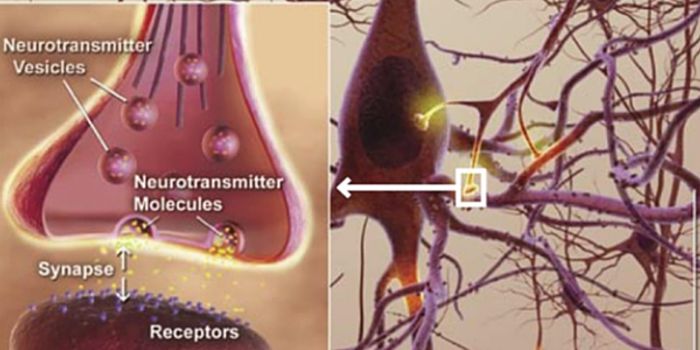

JUN 21, 2016NeuroscienceThe brain has always been referred to as the super computer of the body. Millions of connections happen just to make a s ...